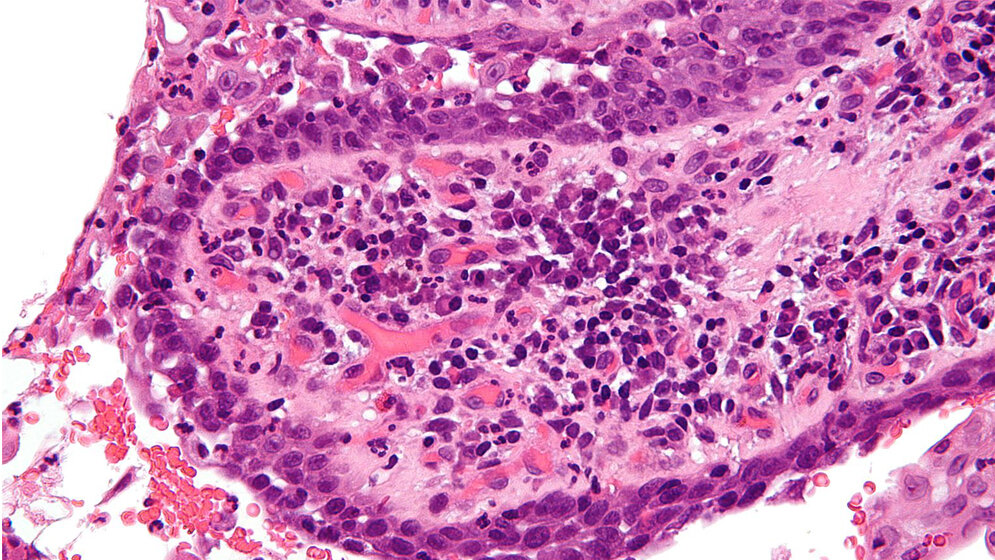

Desmosomen sind knopfartige Strukturen in Zellmembranen, die dazu dienen, benachbarte Zellen fest aneinander zu binden. Man findet sie vor allem in Zellen und Geweben, die einer hohen mechanischen Belastung ausgesetzt sind, beispielsweise in der Haut. „Bei PV werden diese Strukturen durch körpereigene Antikörper angegriffen, so dass die Adhäsion von Hautzellen – die Keratinozyten – und Zellen der Schleimhäute verloren geht“, erläutert Prof. Tikkanen. Die Biochemikerin ergänzt, dass dies zur Bildung von Blasen und Läsionen führe: „Für die betroffenen Patientinnen und Patienten kann das unter Umständen lebensbedrohliche Auswirkungen haben.“

Die Arbeitsgruppe Tikkanen/Banning konnte zeigen, dass Proteine aus der Flotillin-Familie die Zelladhäsion in Keratinozyten regulieren, indem sie den Zusammenbau und die Auflösung von Desmosomen regulieren. Dabei treten Flotilline in direkten Kontakt mit den sogenannten Desmogleinen, die als Haftproteine in Desmosomen dienen. Fehlen die Flotilline, werden Desmogleine verstärkt abgebaut. Verringert sich die Menge von Desmogleinen in den Hautzellen, haften die Keratinozyten deutlich schwächer aneinander als in Anwesenheit von Flotillinen.

Die Autoantikörper beinflussen bei Pemphigus vulgaris jedoch nicht nur die Lokalisation von Desmogleinen, sondern auch von Flotillinen. Dies begünstigt vermutlich die Auflösung von Haftkontakten bei PV. Diese Erkenntnisse über die molekularen Mechanismen bei PV könnten dazu beitragen, Wirkstoffe zu entwickeln, welche die Zellbindung von Keratinozyten bei der Autoimmunerkrankung verstärken und die Hautablösung dadurch verhindern.